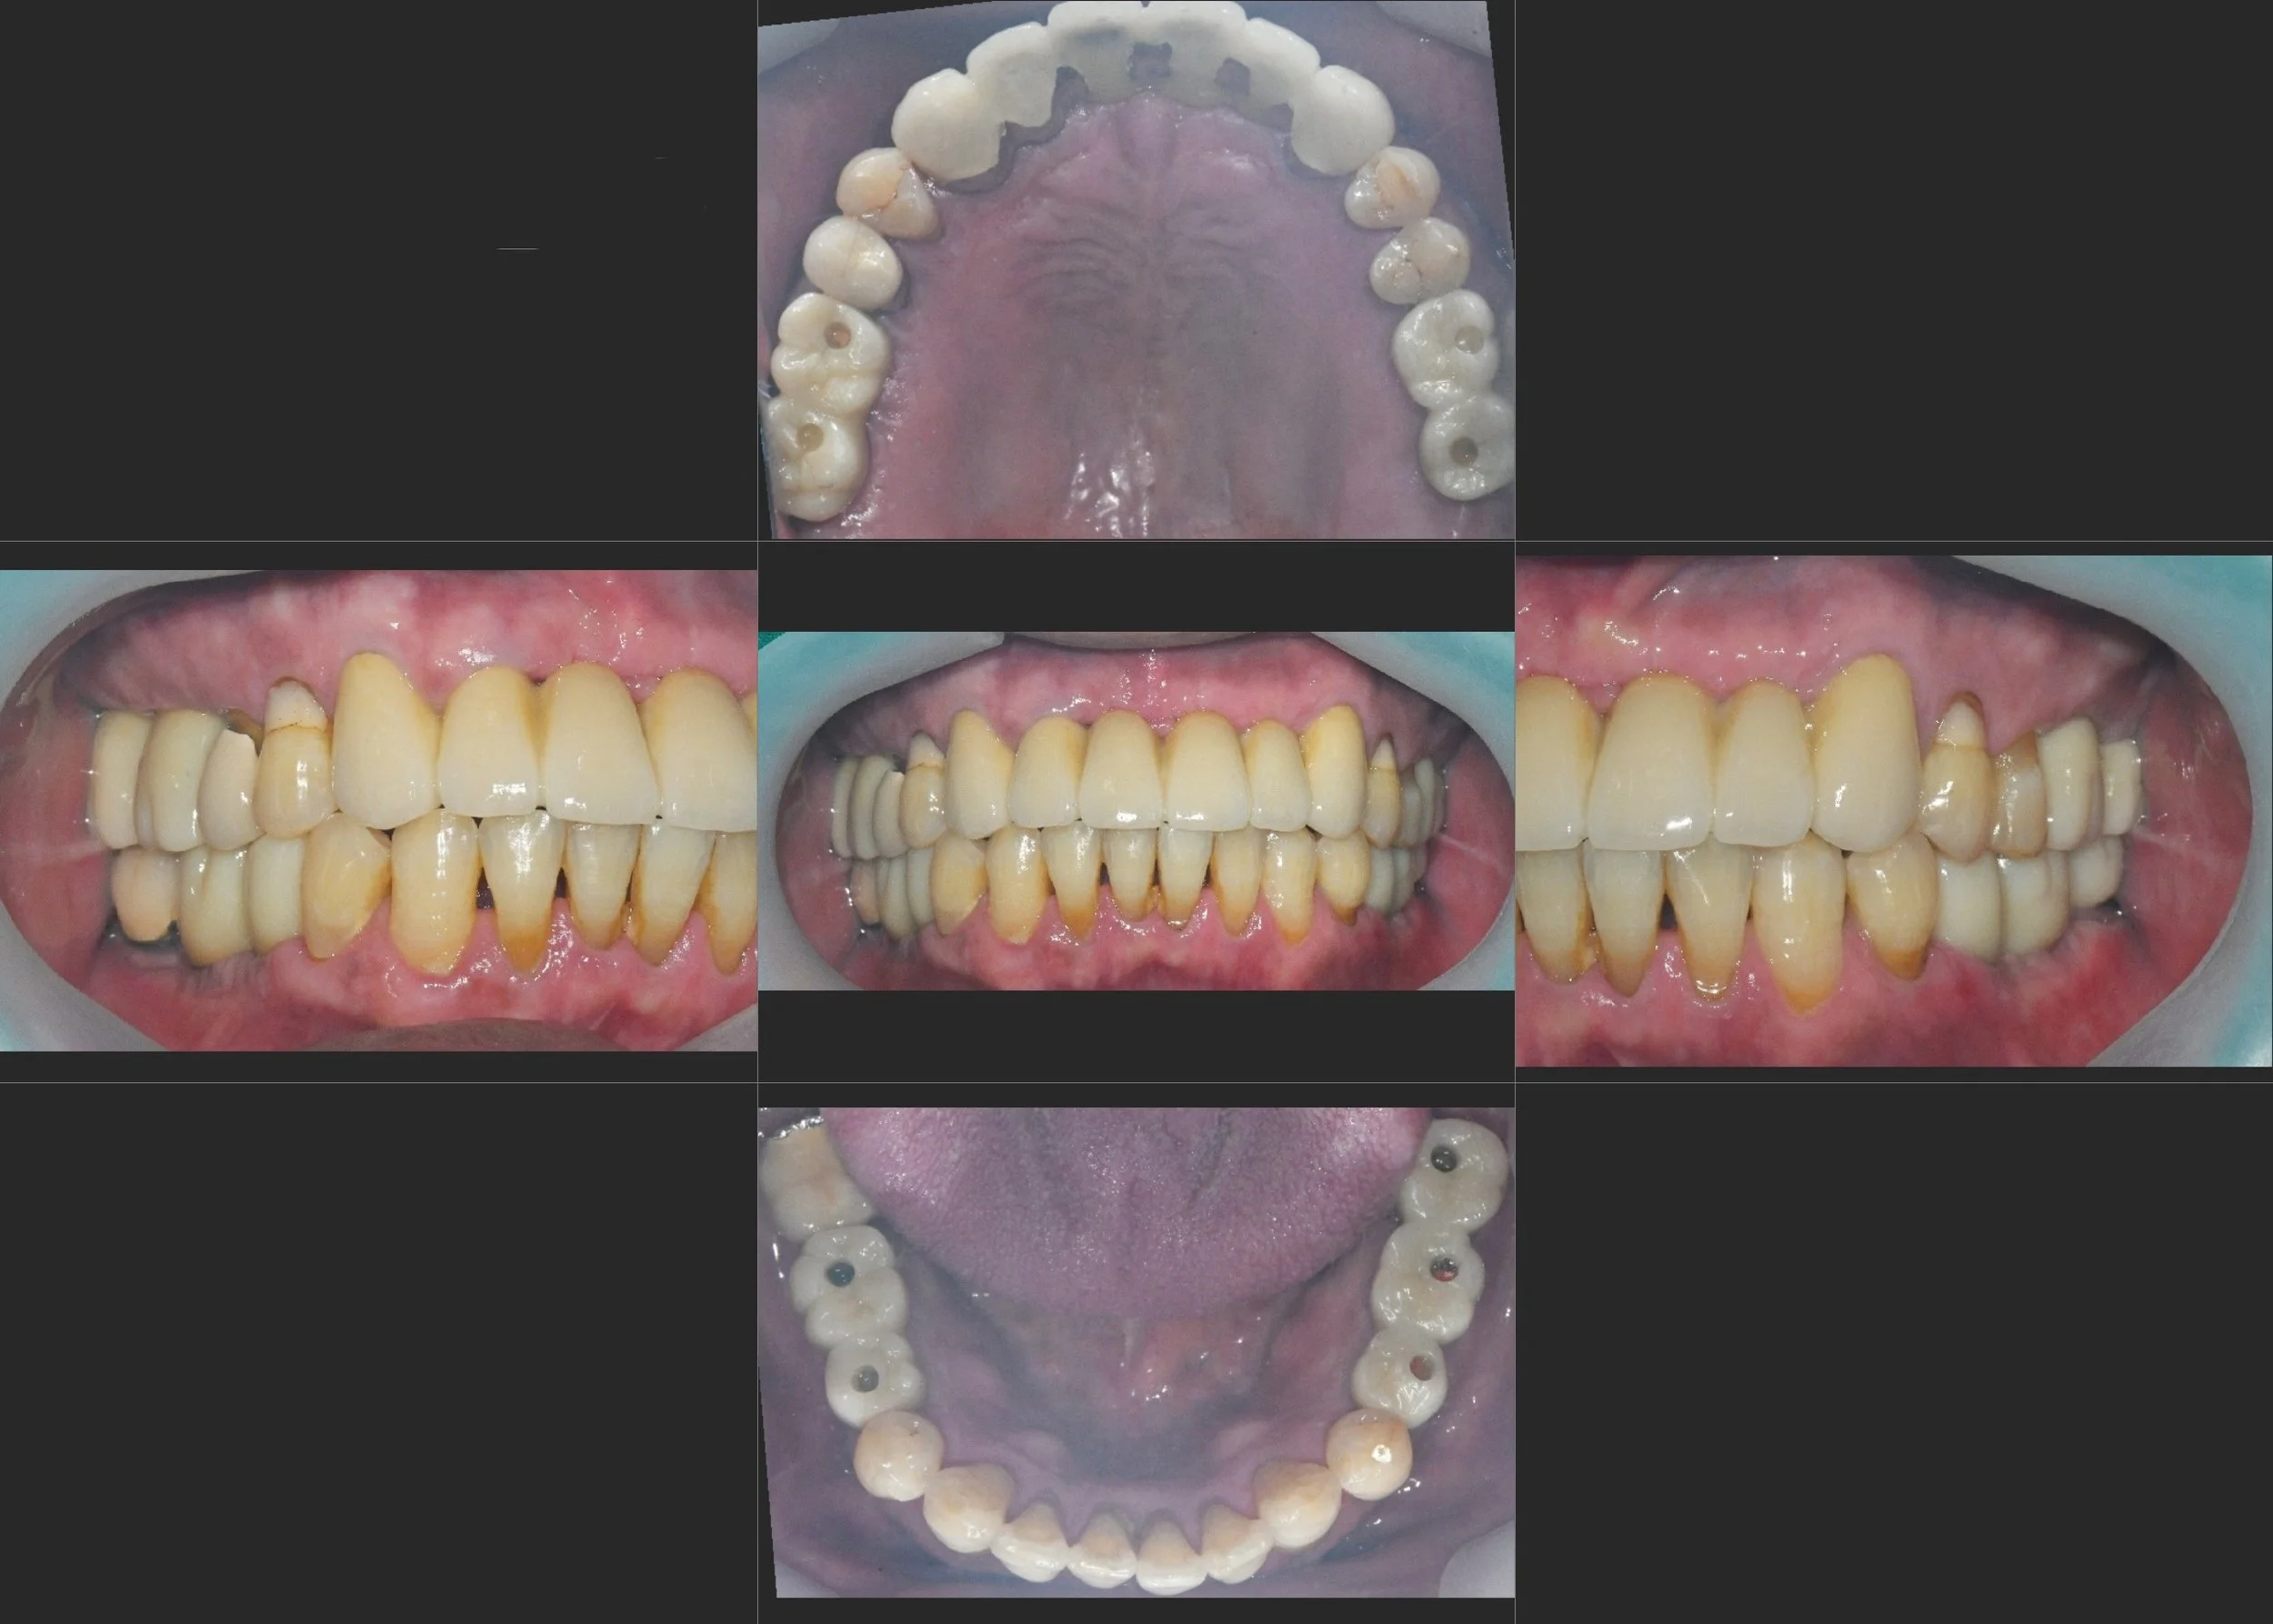

INTRA ORAL - BEFORE

Treatment Objectives

• Periodontal Stabilization: To achieve a healthy, inflammation-free environment through intensive periodontal therapy.

• Prosthetic Re-intervention: To replace failing existing implant crowns and integrate them into a new, stable occlusal scheme.

• Occlusal Curve Correction: To re-establish proper Curve of Spee and Curve of Wilson for optimal masticatory function and interference-free movement.

• Anterior Aesthetic Recovery: To restore the upper anterior segment using high-strength bridges, providing a natural and confident smile.

INTRA ORAL - AFTER